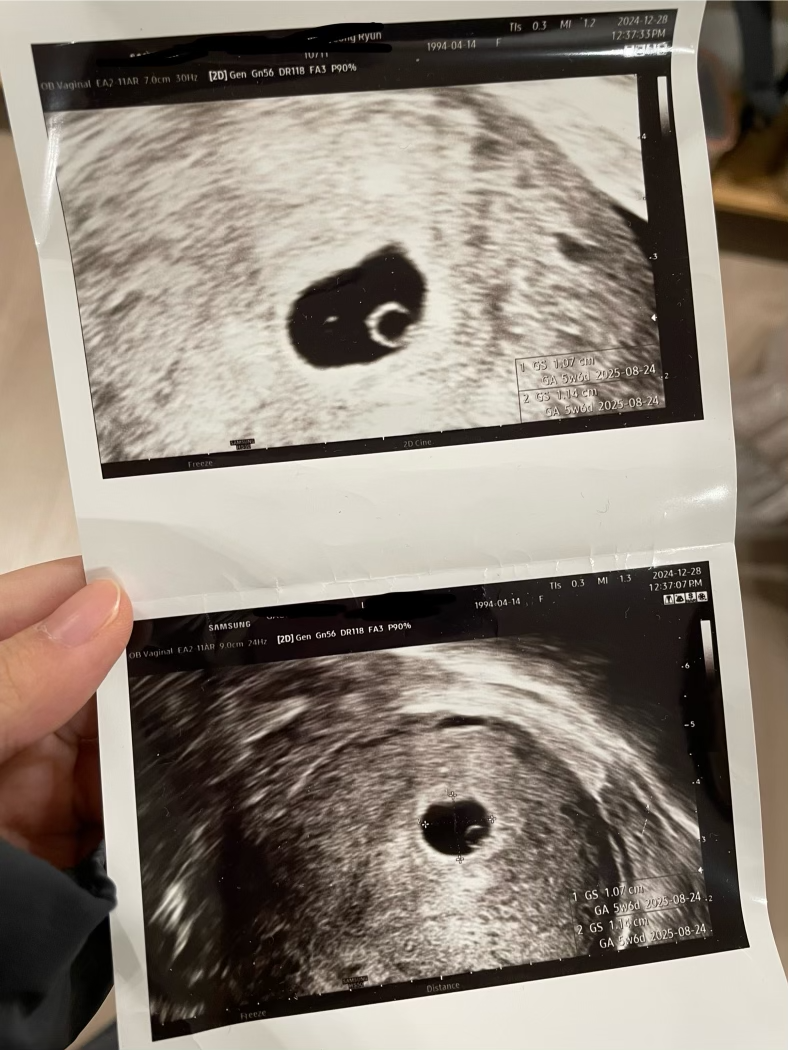

사진이 나오기도 전에 축하해 주시는 선생님. 이게 무슨 소리인가. 벌써 축하해 주신다고? 그리고 얼마 기다리지 않았는데 이제 도저히 부인할 수 없는. 검은색 콩알이 보이는 초음파 사진을 보여주셨다. 사실 뭐가 뭔지도 모를 사진이었는데 1cm짜리 검은색 콩알이 하나 있었다.

IMG_9739.png

"어머 아기집 이쁘네요. 5주인데 이 정도면 아주 건강한 거예요"

어떤 게 이쁘다는 건지는 이해가 가지 않았다. 여하튼 이쁘다고 하시니 좋을 수밖에. 자세히 보니 동그란 아기집과 마찬가지로 동그란 난황이 어쩌면 그렇게 균형 잡혔는지. 임신테스트기 빨간 두 줄로는 동하지 않았던 내 가슴 한 구석에서 어째서 그런지 따땃한 느낌이 들었다. 5주면 아직 태아로도 치지 않고 배아라고 한다. 아직 사람이라고 할 수는 없는 것이다. 그런데 이쁠 수가 없는 그냥 검은색 콩알인데, 왠지 콩알의 가로 세로 비율이 황금비인 것 같다. 아주 동그랗지도 않고, 찌그러지지도 않은 균형 잡힌 비율로 안정적으로 붙어 있는 콩알. 어째서 내 눈에도 벌써 이뻐 보이는 건지..?

병원 접수대에서 임신 5주 차 증명서를 받아서 집으로 향했다. 출산 예정일은 8월 24일. 너무 이르다. 임신 사실을 알게 되면 그때부터 1주 차일 거라고 생각했는데, 왜 갑자기 5주 차나 되었다는 것일까. 집에 가는 길에 내가 다시 물었다.